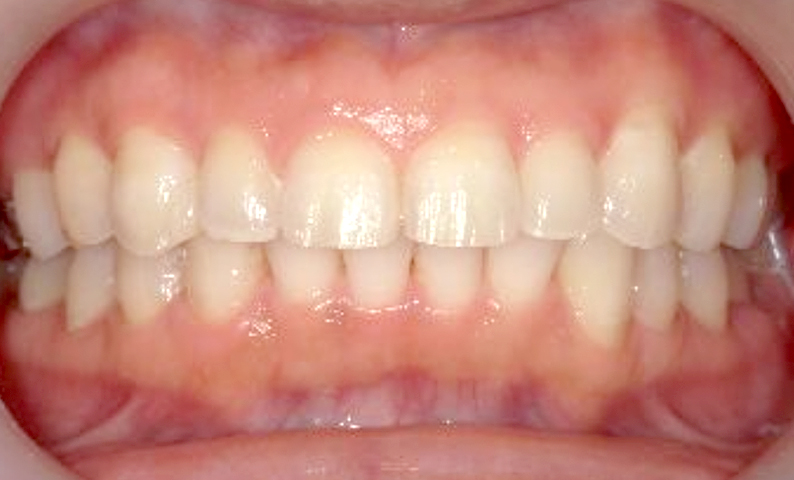

症例_001 前歯「すきっ歯」症例

治療期間:9ヶ月金額:51万円+税20代女性すきっ歯